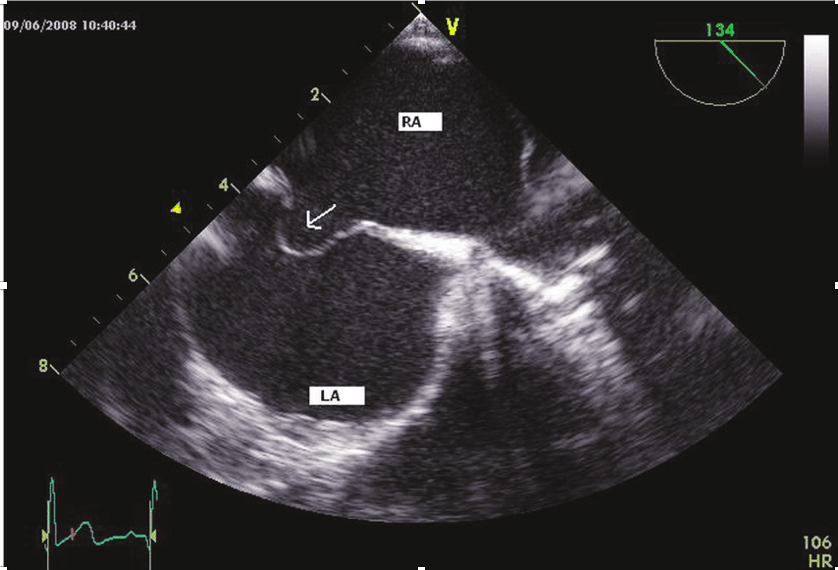

ASD može da bude asimptomatski do 30. ili 40. godine. Postepeno se javljaju dispnea, zamor, palpitacije, zatim atrijalna fibrilacija i eventualno srčano popuštanje. U fizikalnom pregledu naći ćemo: sistolni šum nad pulmonalnim ušćem, holosistolički šum nad apeksom ako se radi o defektu tipa primum. Na EKG-u naći će se inkompletni blok desne grane, dekstrogram kod defekta tipa sekundum, i sinistrogram kod defekta tipa primum. Na RTG cor et pulmo naći ćemo uvećanu desnu pretkomoru, desnu komoru i truncus pulmonalis. Zlatni standard za postavljanje dijagnoze je transezofagealna ehokardiografija.